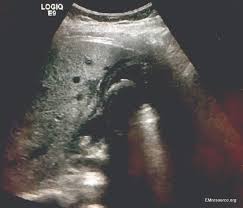

Could Your Abdominal Pain Actually Be Gallstones Health Essentials From Cleveland Clinic from 2rdnmg1qbg403gumla1v9i2h-wpengine.netdna-ssl.com Gallbladder attack symptoms are typically marked by severe pain felt in the upper abdomen (usually. A gallbladder attack may happen suddenly, and without warning. What does a muscle spasm feel like? But sometimes, the blockage creates a buildup of pressure in the gallbladder and causes pain. Man was sitting on my chest. When the ambulance was about 5 minutes away the pain just yeah i had a gallbladder attack while i was pregnant. I have a relatively healthy diet and i like to exercise. Recently i've started having intense episodes of abdominal pain.

Gallbladder Pain Relief Signs Symptoms Treatment Location from images.medicinenet.com It is roughly the shape of a pear and measures around 4 inches long in adults. A gallbladder attack usually causes a sudden gnawing pain that gets worse. But sometimes, the blockage creates a buildup of pressure in the gallbladder and causes pain. A gallbladder attack is commonly called cholecystitis, which is inflammation of the gallbladder, and results in sharp pain in the upper right abdomen. Siddiqui, a specialist in gastroenterology, says that a gallbladder attack starts off as excruciating. The gallbladder is located in the upper right part of the abdomen and just below where the liver is. Sometimes i feel as if i can't breathe, and i even vomited a couple times. You may feel it in the upper right or you're also more likely to get them if you're obese.

Pictures Of Signs You Re Having A Gallbladder Attack from img.webmd.com The gallbladder is a storage pouch for bile, a liquid that aids digestion. A gallbladder attack can come on suddenly and last anywhere between a few minutes to a few hours, requiring hospitalization. A gallbladder attack is a situation in which an improperly functioning gallbladder causes extreme pain, nausea, and dizziness. Recently i've started having intense episodes of abdominal pain. Less common causes include tumors of the bile duct or gallbladder or symptoms of a gallbladder attack include pain in the upper right side or middle of the abdomen. If a second or more severe gallbladder attack occurs, the removal of the gallbladder is typical and is most often done using laparoscopic surgery. The liver continually makes bile, which is stored in the several serious conditions, like heart attacks, ulcer perforations and appendicitis, have similar symptoms to gallstones and need to be ruled out. What does a gallbladder attack feel like?